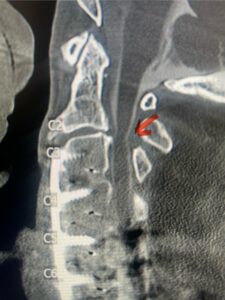

Fig. 3: Sagittal T2-weighted cervical MRI demonstrating a significant disc osteophyte complex causing spinal cord compression at C 5 6 with extensive myelomalacia (red arrow)

A 37-year-old male police officer complained of a one-month history of difficulty with his balance and leg weakness. He complained of achiness in his legs. He also complained of bilateral arm weakness and numbness of his hands. He was also having difficulty writing due to the weakness. Patient had an MRI of the cervical spine which demonstrated a disc/osteophyte at C56 causing spinal cord compression and concurrent myelomalacia (Fig. 3). Patient underwent an anterior cervical discectomy with a cage and plate (Fig. 4). He tolerated the procedure well with improved numbness and weakness. This is a young person with fairly extensive myelomalacia and a fairly rapid development of symptoms. For this it was felt surgery was indicated. How he will do will depend on how much of his symptoms was caused by the compressive component or intrinsic damage to the spinal cord. As a rule, patients generally improve to some extent quickly; but their recovery of their spinal cord function can sometimes take up to 2 years to realize the extent of their improvement. Patients have to be patient with themselves in terms of their expected recovery.